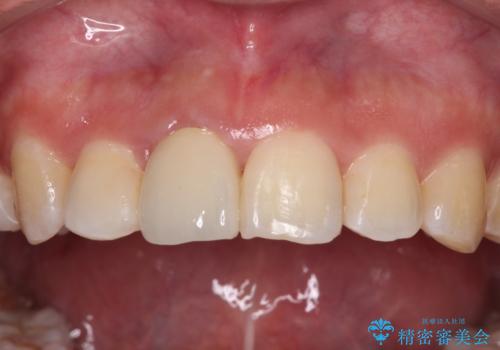

虫歯と抜いたままの奥歯とデコボコの前歯 総合歯科治療

- 放置した虫歯や抜いたままの奥歯、前歯のデコボコを気にして来院された患者様です。

口元の突出感は少なく、下顎の叢生は軽微なものであったので、叢生の強い上顎左右の小臼歯を1本ずつ抜歯し、ワイヤー装置にて矯正治療を行うこととしました。

矯正治療を行う前に、根管治療の必要な上顎前歯と下顎大臼歯の根管治療を行い、矯正治療の途中で下顎の欠損部にインプラント埋入することとし、矯正治療後に補綴治療を行うこととしました。

矯正治療をしたいと思っていたが、放置している虫歯が多いため、どこに相談に行けば良いのか分からずにいたそうですが、当院の総合歯科診療を見て来院されたそうです。

矯正治療中にインプラント埋入を行うなど、余計な時間や無駄のない治療を行うことができました。